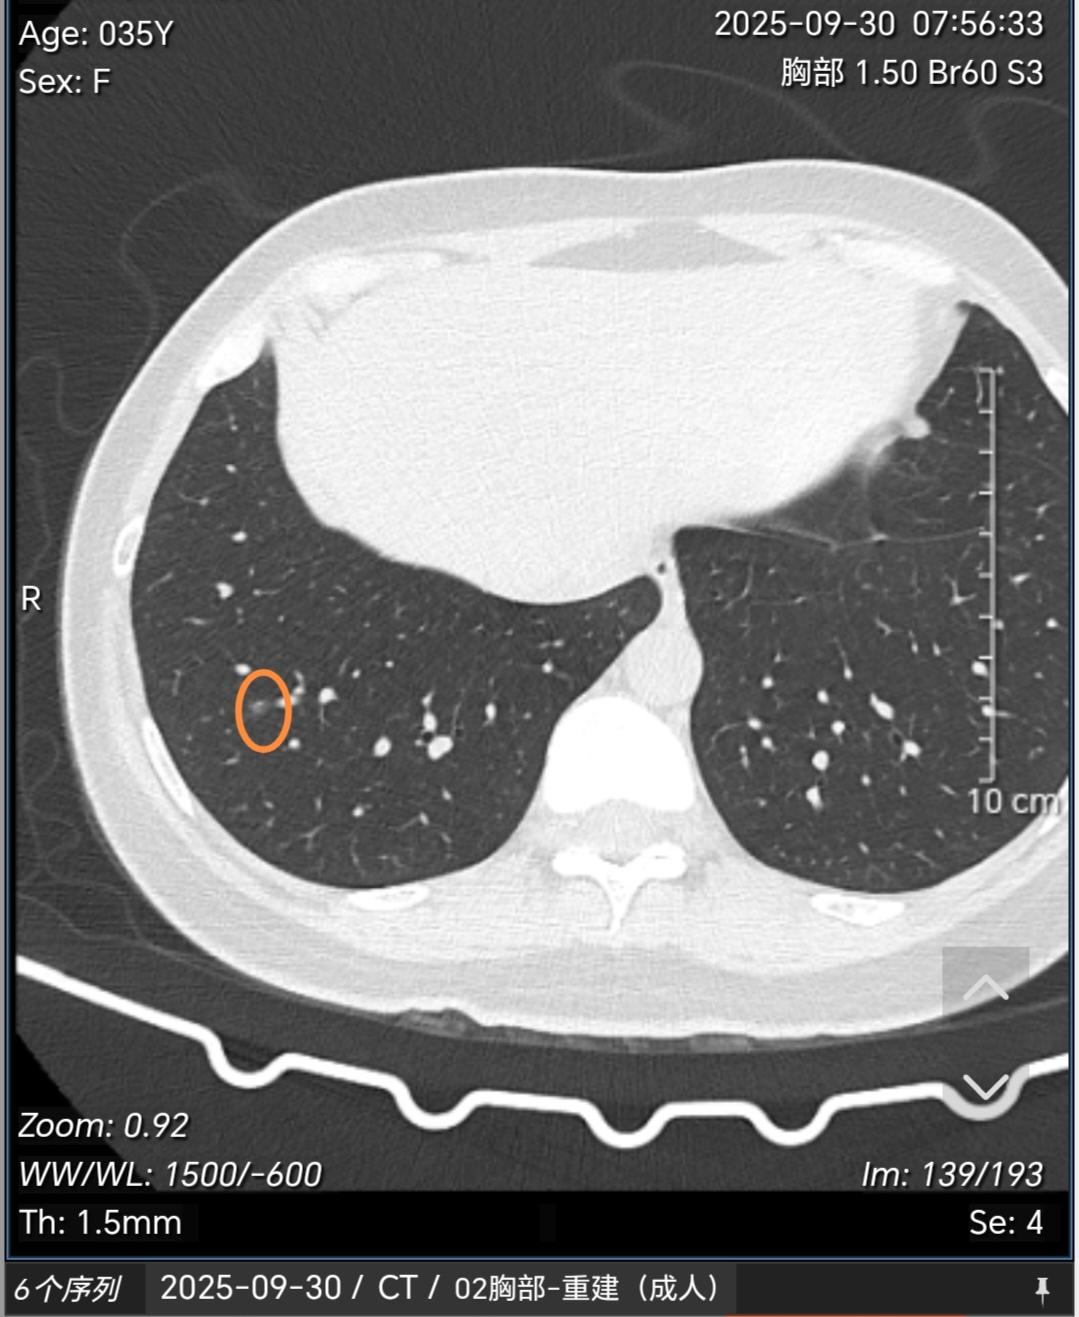

多发磨玻璃结节常见原因有哪些?如何处理?这种多发磨玻璃结节如果经半年左右观察没有明显缩小或消失一般多考虑是肿瘤性的,这类多发肿瘤性的磨玻璃结节最常见的原因就是遗传(基因易感体质),再者就是职业原因接触一些高致癌物质(苯、酚、氡、放射性物质、重金属等)。其他烟、空气污染等所致的肿瘤多见的是单发。那么对于这类结节怎么处理?对于这类多发的,一般手术很难切净,所以建议先观察,后续发现哪个结节有增大再以这个结节为主进行包括手术、消融或立体定向放疗在内的综合治疗策略。